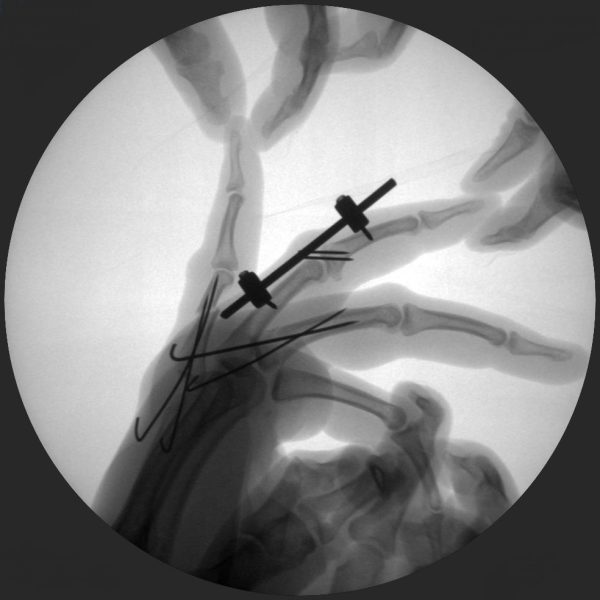

CRIF - Closed reduction internal fixation

ORIF - Open reduction internal fixation

Clinical Evidence

Skan-C is a great C-arm for orthopaedic treatments for several reasons